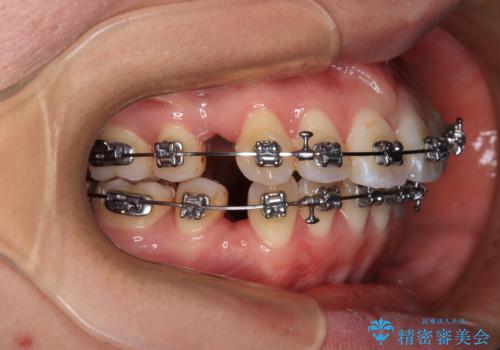

- 矯正装置

- メタルブラケット

- 上下の出っ歯を気にして来院された患者様です。

口元を積極的に引っ込めるために、上下左右の第一小臼歯を4本抜歯することとしました。

また、上下前歯は舌の突出癖による開咬となっていたため、舌のトレーニングを徹底するよう指示しました。